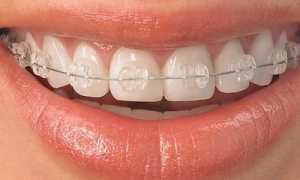

- установка брекет-системы, протезов, мостов;

Ортодонтическое

Такой вид экстракции применяется во время ортодонтического лечения (исправление прикуса, постановка коронок). Решение о необходимости удаления здоровых коренных зубов принимает специалист после нескольких консультаций и рентгеновских снимков. Удаление может производиться с использованием как щипцов, так и скальпеля.